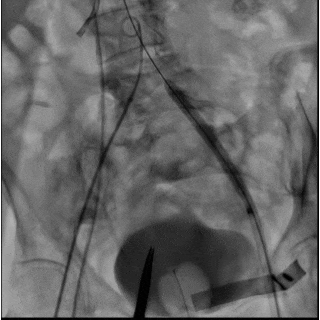

(A)使用 21 mm TRUE balloon 行主动脉瓣预扩张。于钙化的 Evolut R valve 瓣叶水平可见明显“球囊腰征”(白色箭头),提示充盈过程中存在显著阻力。(B)植入 23 mm SAPIEN 3 Ultra RESILIA valve(S3UR)过程中发生球囊破裂。球囊远端可见造影剂积聚(白色箭头),形成类似“伞状”外观,提示存在水平撕裂。23 mm 瓣膜未完全释放(白色箭头)。(C)对侧入路行髂动脉造影。可见左侧髂总动脉夹层,但无活动性造影剂外渗(白色箭头)。(D)使用 23 mm TRUE balloon 对未完全扩张的 S3UR 瓣膜进行后扩张。(E)血管内干预后髂动脉造影。将 16F eSheath 回撤至左侧髂外动脉,并于夹层的髂总动脉内植入一枚 8 × 59 mm VBX 覆膜支架(白色双向箭头)。(F)血管内干预后股动脉造影。左侧股总动脉穿刺通路采用 7 × 50 mm Viabahn stent graft 进行封闭(白色双向箭头)。最终造影显示无造影剂外渗,血流通畅。

经左股动脉将输送系统及鞘管整体取出,随后更换为16F 鞘管以压迫可能的血管损伤。经对侧髂动脉造影显示左侧髂总动脉夹层,但无活动性造影剂外渗(图6C,视频8)。术中血流动力学始终稳定。

将16F鞘管回撤至左髂外动脉水平,并植入一枚8×59mm VBX 覆膜支架用以修复左侧髂总动脉夹层(图6E,视频10和11)。左股动脉穿刺口采用7×50mm Viabahn 覆膜支架进行封闭(图6F,视频12)。最终造影示无造影剂外渗,血流通畅(视频13)。